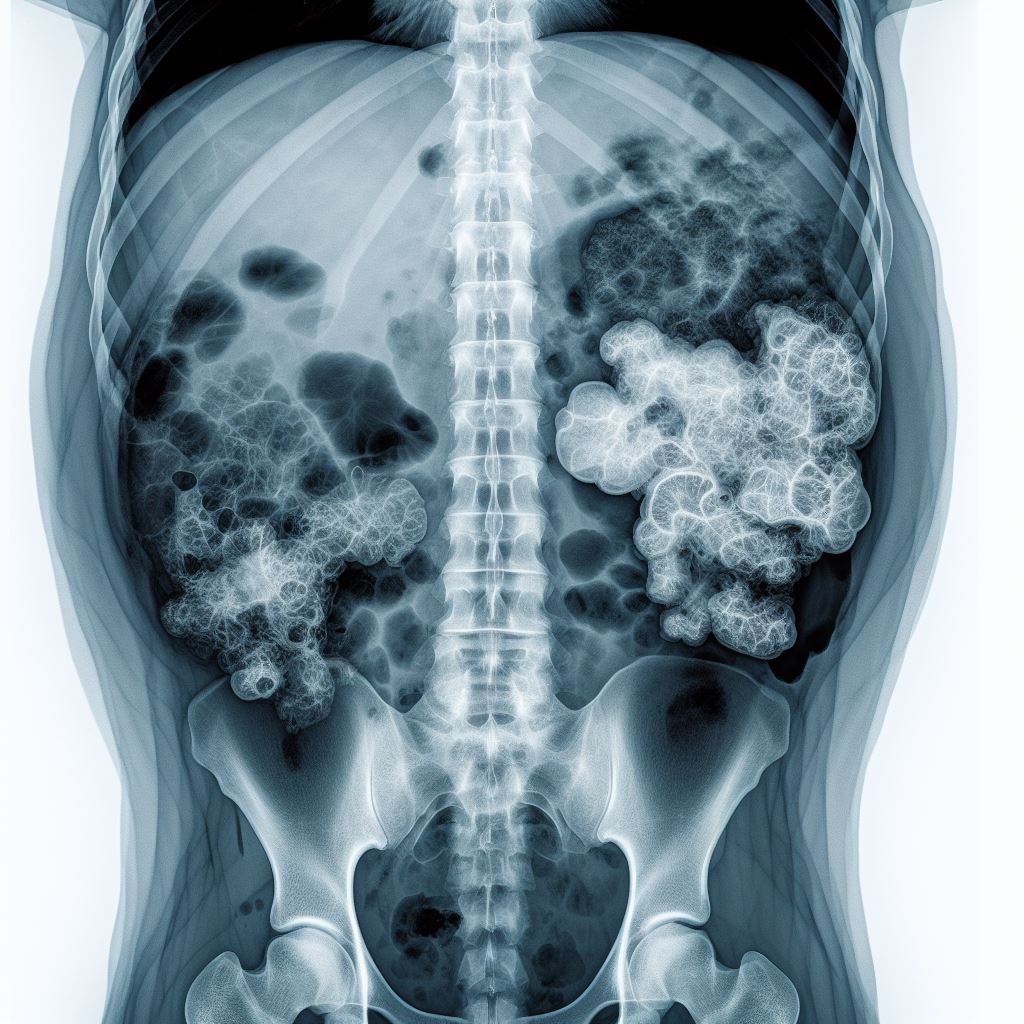

영상 진단 방법 (X-레이, 초음파)

췌장염의 진단에는 영상 진단 방법이 널리 사용됩니다. X-레이와 초음파는 강아지의 내부를 시각적으로 확인할 수 있는 도구로, 췌장의 크기와 모양, 그리고 주변 구조의 이상 여부를 확인하는 데 매우 유용합니다. 이러한 영상 진단 방법은 췌장염의 정도를 평가하는데 도움이 되며, 진단의 정확성을 높입니다. 또한, 영상 진단은 증상이 있는 강아지의 내부 상태를 직접 확인하고, 문제가 발생한 부위를 정확히 파악하는데 중요한 역할을 합니다.